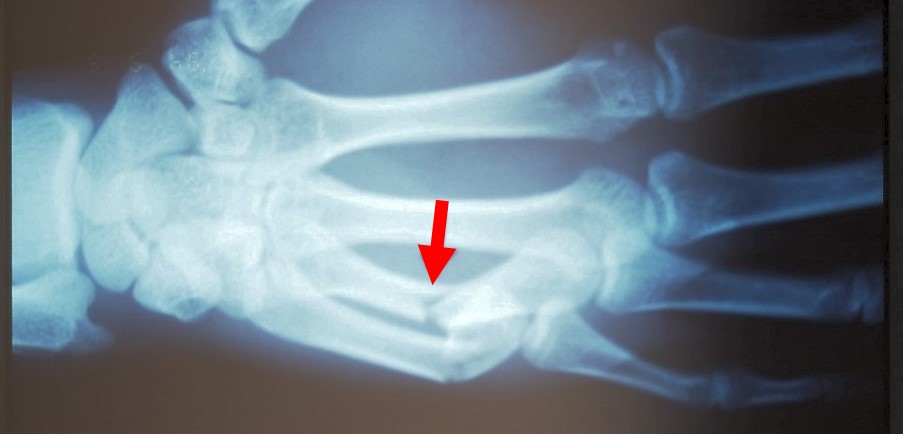

写真2 ボクサー骨折のレントゲン写真

レントゲン

中手骨の頸部に骨折線があり、背側突の屈曲変形を呈します(写真2)。この変形は、骨間筋、指屈筋腱、手根伸筋などの作用で骨が転位したため引き起こされます。